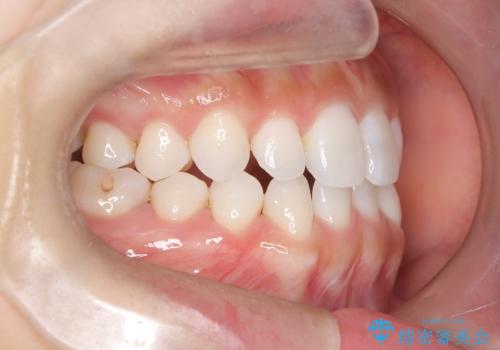

- 空隙歯列を主訴に来院された患者様です。

ばらけている空隙を一箇所に集めながら咬合や正中を改善して最後に補綴治療を行なっています。

右上の臼歯クロスバイトは骨格生のため、そのままにしています。